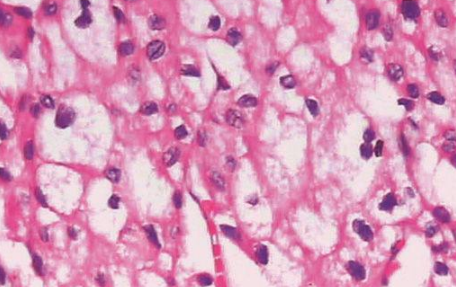

肾嫌色细胞癌是一种非常见的肾细胞恶性肿瘤,但与普通的肾细胞恶性肿瘤相比,它的恶性程度相对较低,它的形态比较特殊,恶性程度不高,根据临床医学认识,它起源于肾集合管上皮,目前在治疗此类恶性肿瘤时,大多会进行根治性切除。

全肾脏切除后往往预后效果好,与同期其他类型的恶性肿瘤相比,它的5年生存期比例相对较大。

对于患者来说,做到早发现早治疗相当重要。它的早期症状相对较少,但是肿瘤增大后可以出现明显的血尿、持续性腰痛,同时多伴有腹部包块,以上症状也被临床医学上称之为肾癌的三联征,若出现以上症状要引起重视。